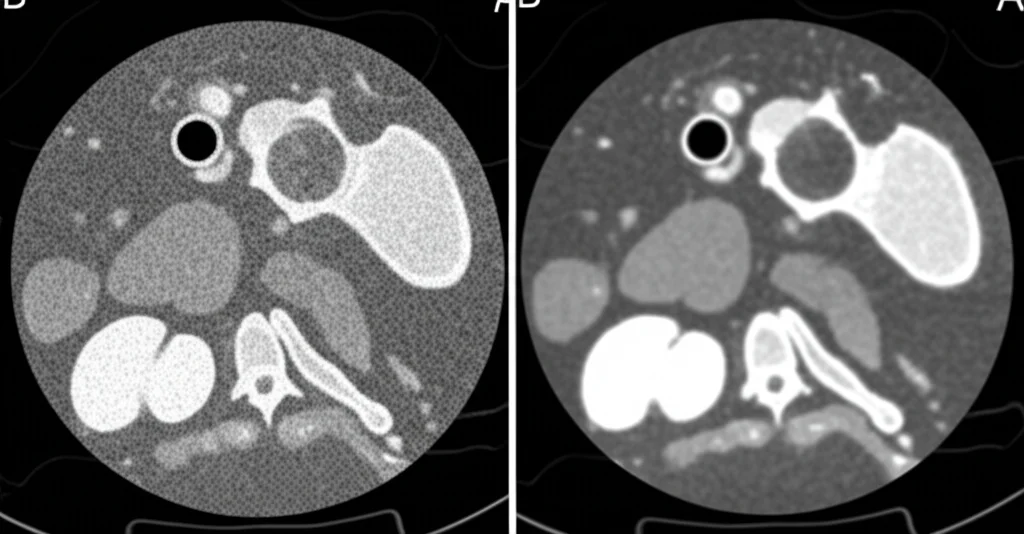

Cosa significa? Immaginate di avere i dati grezzi di una scansione PET acquisita con la dose standard (full statistics). La “decimazione” è un processo che simula una riduzione della dose iniettata scartando casualmente una parte di questi dati prima di ricostruire l’immagine. Possiamo così creare immagini come se fossero state acquisite con il 30%, il 10%, il 5%, il 2% o addirittura l’1% della dose standard! Ovviamente, più scendiamo con la dose simulata, più l’immagine diventa rumorosa e difficile da leggere.

Ed ecco che entra in gioco l’AI! Abbiamo utilizzato un algoritmo di CNN addestrato appositamente per “ripulire” queste immagini a bassa dose (denoising). L’obiettivo è rimuovere il rumore di fondo mantenendo, o addirittura esaltando, il segnale delle lesioni, restituendo un’immagine di qualità simile a quella ottenuta con la dose piena. Una specie di “restauro” digitale super intelligente.

Nel nostro studio retrospettivo, abbiamo preso le scansioni PET/CT di 49 pazienti che avevano almeno una lesione polmonare (in totale ne abbiamo analizzate 141). Abbiamo generato le immagini PET simulate a diverse dosi (100%, 30%, 10%, 5%, 2%, 1%) sia nella versione “originale” rumorosa (non-denoised) sia in quella “ripulita” dall’AI (denoised). In totale, ben 588 ricostruzioni diverse!